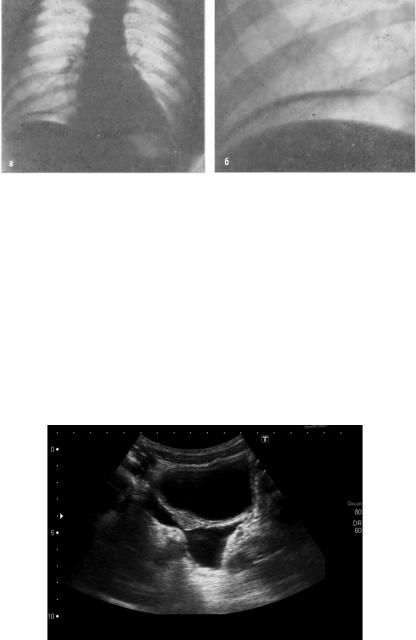

При обзорной рентгенографии брюшной полости можно выявить свободный газ при перфорации полого органа (рис. 2), уровни жидкости и расширенные петли кишки при непроходимости (как механической, которая может явиться причиной перитонита, так

Рис. 2. Пневмоперитонеум. Газ под правым куполом диафрагмы

и паралитической — признаком​ синдрома кишечной недостаточности, развившемся вследствие перитонита).

Современное ультразвуковое исследование способно выявить как признаки самого перитонита, так и заболевания, явившегося его источником (рис. 3). Признаками перитонита является наличие свободной жидкости в брюшной полости, для уточнения характера которой выполняют пункцию ее под контролем УЗИ, наличие в пунктате гноя, фибрина, кишечного содержимого делает диагноз очевидным. Другим ультразвуковым признаком перитонита может быть визуализация расширенных, вяло или вовсе не перистальтирующих петель тонкой кишки, что свидетельствует о синдроме кишечной недостаточности.

Рис. 3. На УЗИ визуализируется жидкость в брюшной полости (более 2 л)